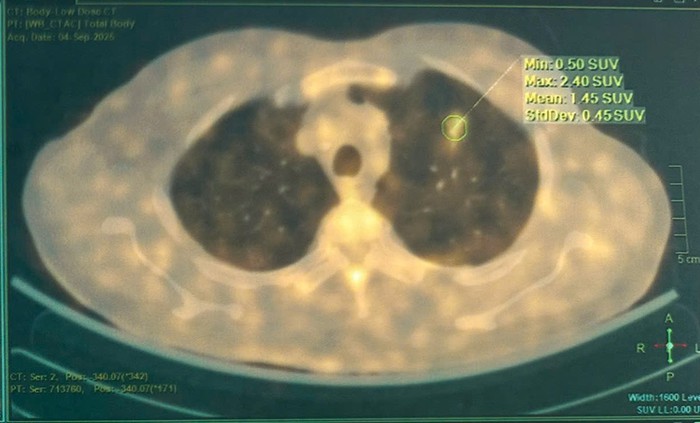

Các xét nghiệm máu, sinh hóa và đông máu đều trong giới hạn bình thường. Marker Cyfra 21-1 tăng nhẹ - một trong những chỉ dấu liên quan đến ung thư phổi. Trong khi đó, CT ngực ghi nhận tổn thương kính mờ bờ tua gai, còn CT bụng phát hiện giãn đài bể thận và sỏi niệu quản.

Điểm đặc biệt là hệ thống AI phân tích hình ảnh của bệnh viện đã xác định tổn thương phổi của bệnh nhân có xác suất ác tính lên tới 97%. Kết quả này khiến hội đồng chuyên môn phải xem xét can thiệp ngay thay vì tiếp tục theo dõi. Sau hội chẩn, bệnh viện quyết định chỉ định phẫu thuật nội soi cắt thùy trên phổi trái và nạo vét hạch.

Hình ảnh vài đám tổn thương dạng kính mờ bờ tua gai ở thùy trên phổi trái